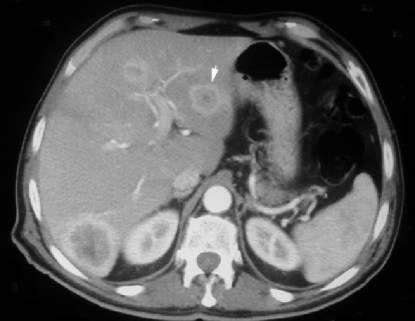

SIGNO DEL PUNTO BRILLANTE

Signo de hemangioma de comportamiento atípico. En el estudio de TC helicoidal de doble fase (fase arterial hepática y fase venosa portal), la mayoría de hemangiomas presentan un realce más precoz en la periferia y más tardío en el centro, pero hay hemangiomas atípicos que muestran una hipodensidad mantenida en las dos fases. La mayor parte de estos últimos muestran un punto brillante o más en al menos una de las dos fases.

El signo representa el relleno de contraste de un espacio vascular (flecha).

La referencia bibliográfica de este signo es: Hyun-Jung Jang y cols. Atypical small hemangiomas of the liver: «bright dot» sign at two-phase spiral CT. Radiology 1998; 208:543-548.